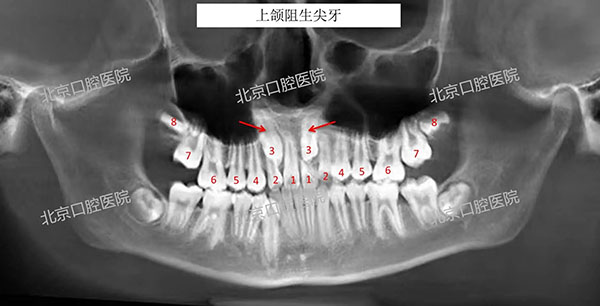

X光片影像发现,上颌虎牙把门牙的牙根都顶坏了,其中一位小朋友有两颗上前门牙都保不住了。

乳尖牙是所有乳牙中最后替换的,如果存在恒尖牙萌出空间不足、牙胚发育异常、乳尖牙滞留、外伤或全身疾病等,使恒尖牙在颌骨内萌出方向异常,或萌出受到阻碍,就会导致其无法正常萌出而发生阻生,多见于上颌尖牙。

萌出方向异常阻生尖牙,长期刺激周围上皮组织发生囊性变,会持续挤压邻牙(多为侧切牙、中切牙、第一前磨牙),导致邻牙牙根吸收变短、严重时导致邻牙松动、脱落。